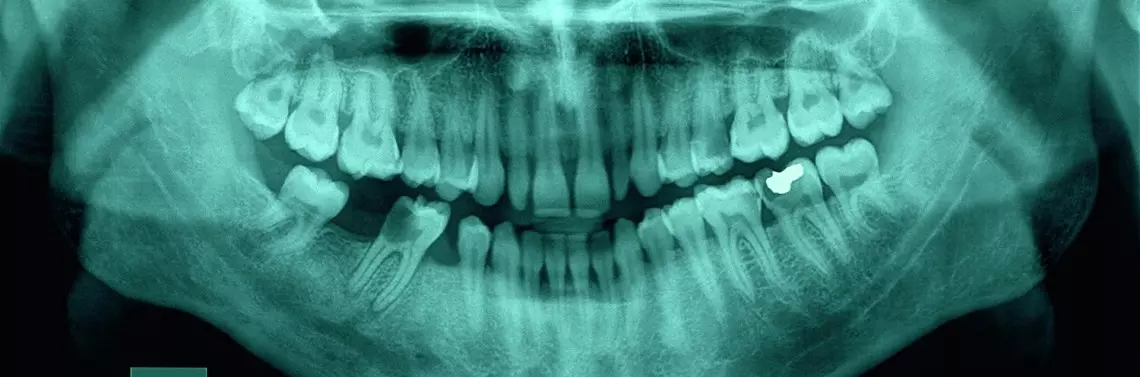

*Zdj. 2A - 5C - Przypadki kliniczne pracy pilnikami HyFlex, Coltene Whaladent

Współczesna endodoncja zakłada minimalnie inwazyjną preparację zęba w zakresie części koronowej i korzeniowej, a stosowanie pilników z minimalną stożkowatością 4% staje się bezwzględnym minimum w celu prawidłowej dezynfekcji systemu kanałowego. Jednymi z nowszych systemów o innowacyjnym podejściu do opracowywania kanałów korzeniowych są pilniki HyFlex CM. System regenerujących się pilników HyFlex jest jednym z nielicznych pracujących na zasadzie koncepcji minimalnie inwazyjnej endodoncji, niepowodującej nadmiernego wyprostowania światła kanału. Są one wyjątkowo elastyczne, co zapewnia im lepsze dopasowanie do kanału. Bardzo istotną własnością pilników HyFlex jest ich rozkręcanie podczas opracowania kanału. Taka własność powoduje, że lekarz w lepszy sposób kontroluje pracę pilnika i widzi jego większe lub mniejsze zużycie. Po pracy wystarczy poddać pilnik działaniu wysokiej temperatury, wraca on wtedy do swojej pierwotnej postaci, a brak takiej reakcji świadczy o wysokim stopniu zużycia, czyli informuje lekarza, że instrument trzeba wyrzucić.

Pilniki niklowo-tytanowe HyFlex Controlled Memory (kontrolowana pamięć) wyprodukowano przy wykorzystaniu unikalnego procesu kontrolującego pamięć materiału, co pozwala na uzyskanie niezwykłej elastyczności pilników, a jednocześnie nie mają one pamięci kształtu tradycyjnych pilników niklowo-tytanowych. Dzięki temu pilnik może bardzo dokładnie dopasowywać się do budowy anatomicznej kanału, zmniejszając ryzyko powstawania stopni, transportacji lub perforacji. Ponadto pilniki można wstępnie doginać, podobnie jak w przypadku pilników stalowych. Jest to szczególnie przydatne w przypadku kanałów korzeniowych z nagłymi krzywiznami w celu uniknięcia powstawania stopni.

Pilniki HyFlex CM można stosować przy użyciu techniki crown-down, step-back lub zalecanej techniki jednej długości, w której wszystkie pilniki wykorzystywane są – z wyjątkiem krótkiego pilnika do otwarcia kanału – do długości roboczej, zapewnia ona dokładne dopasowane opracowanie do budowy anatomicznej. Zalecane jest stosowanie kątnicy wolnoobrotowej przy 500 rpm i momencie obrotowym do 2,5 Ncm. W skład zestawu wchodzi 6 pilników, jednak w zależności od sytuacji klinicznej liczba pilników może być zmniejszona do 3 instrumentów, należy wtedy zastosować metodę crow-down. Pilniki HyFlex reagują na nadmierny opór wyprostowaniem spiral, co pozwala uniknąć zaklinowania w kanale i z tego powodu zwiększa odporność na złamanie.